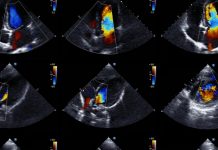

GE – ウィズコロナに最適化する「AI搭載ポイントオブケア超音波」(POCUS)

超音波装置の小型化・携帯型への進化により、ポイントオブケア超音波(POCUS)という概念が浸透してきた。それは超音波診断を専門にしない臨床医でも、観察する所見の焦点を絞ることにより、ベッドサイドで積極的に超音波検査を実施する臨床風景の到来を意味する。またPOCUSは現場で簡易に実施できる性質上、ウィズコロナ時代のベッドサイド診療に適している。

GEヘルスケアは30日付ニュースリリースで、同社の最新POCUSシステム Venue Fit、およびシリーズ製品のVenueとVenue Goに対して、心臓超音波用AIツール「RealTime EF」の搭載を発表している。RealTime EFは、心臓が血液を送り出す効率を示す駆出率(EF: ejection fraction)を、スキャン中にリアルタイムで連続的に自動計算する業界最先端のAIツールである。また今回の発表で紹介された同時搭載ツールには、「Lung Sweep(肺全体のダイナミックなパノラマビューを迅速に視覚化)」「Renal Diagram(腎臓の超音波画像にラベル付けするドキュメントツール)」が挙げられている。

COVID-19の拡大を背景として、病棟内外でPOCUSに対する需要は高まり、GEヘルスケアでは既存製品Venue Goの受注が2020年、前年比で5倍以上に増加したという。GEヘルスケアのPOCUS部門でジェネラルマネージャーを務めるDietmar Seifriedsberger氏は「この1年でPOCUSは、直感的な製品デザインとAIによる診断能力で、臨床医のベッドサイド診療で重要な位置を占めるようになった」と語っている。